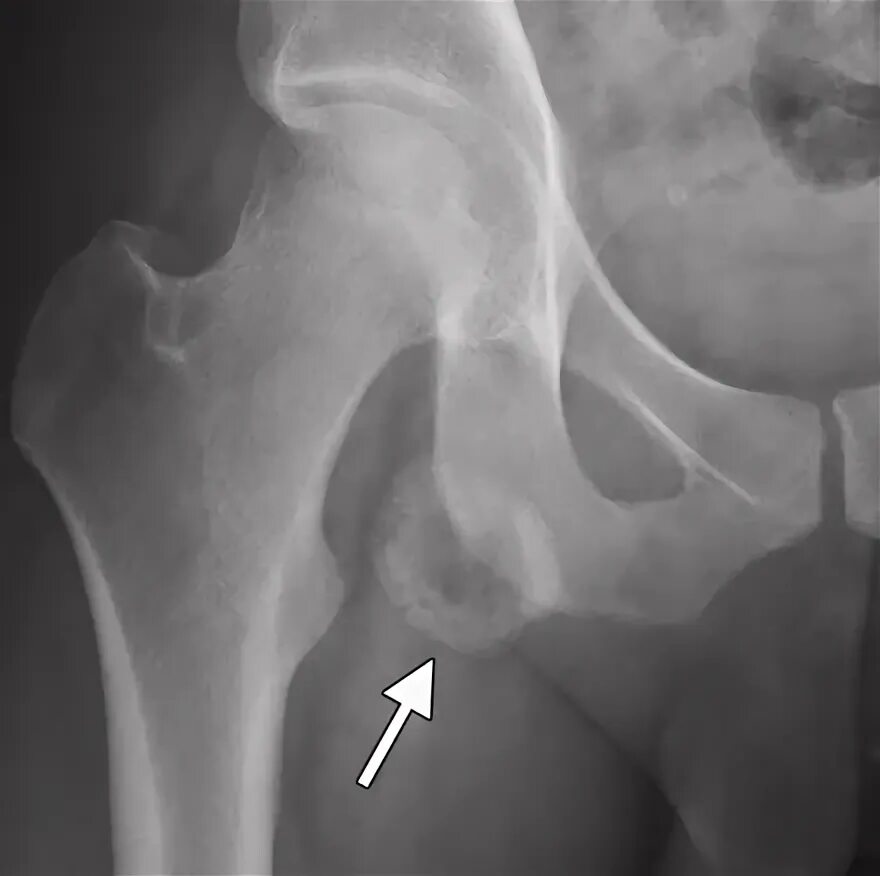

Оссифицированный миозит